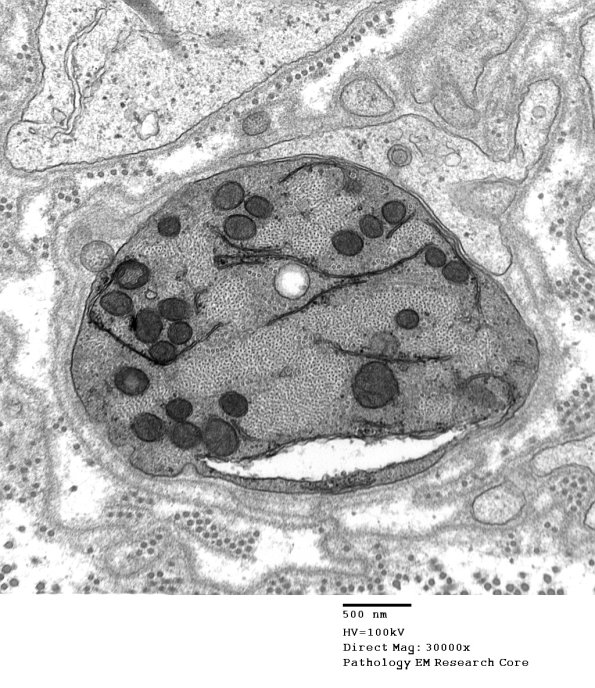

4B13,14 The axon shows a striking cytoskeleton and an invagination of the axolemma (arrow). (electron micrographs)